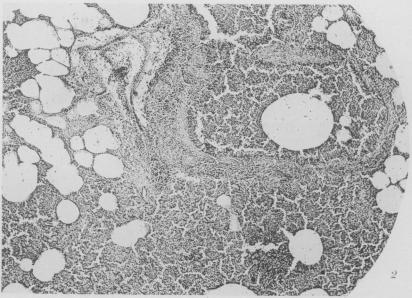

Studies in Canine Distemper.

J Med Res. 1913 Jan;27(3):291-364.7.